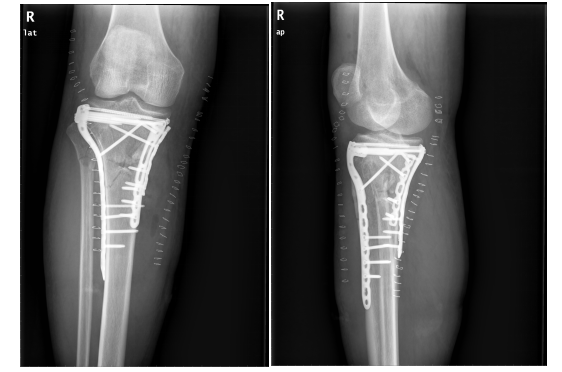

骨折是我们在日常生活中常见的一种疾病,通过手术治疗往往可以达到稳定的固定作用。手术固然重要,但术后功能康复亦不能忽视。小编最近就遇到一位胫骨平台骨折患者,该患者在4个月前发生了车祸导致胫骨平台骨折,并进行切开复位内固定手术治疗。但由于在术后一直畏痛少动,未进行积极地康复治疗,致使患侧膝关节难以像健侧一样伸直,下肢功能急剧下降。为了避免出现以上情况,今天小编就与您分享,胫骨平台骨折术后该如何正确康复。

胫骨平台是膝关节重要的负荷组成部分,也是膝关节创伤中最常见的骨折之一,多发生于强烈的外翻和内翻应力合并轴向载荷时,同时股骨髁对其下胫骨平台有压力和剪切力,可造成劈裂骨折、塌陷骨折或两者兼有。当发生胫骨平台骨折后,需要通过手术切开复位固定,术后要及时进行康复训练,以加快骨折愈合,促进患肢功能恢复。

1.拍摄膝关节X光片复查,并根据骨折线愈合情况及专业医生建议决定是否开始进行患肢负重练习。